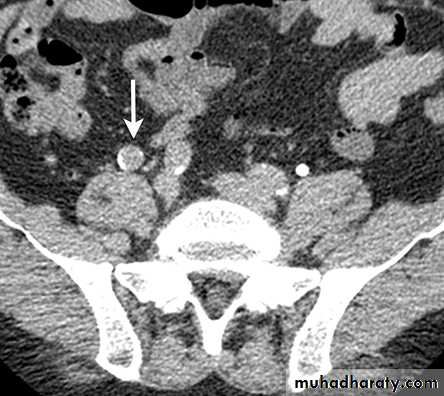

CT scanContrast enhanced CT scan through the kidneys in nephrogram phase 90-100 seconds following contrast administration and would show renal lesions well.

Contrast enhanced CT scan through the kidneys in pyelogram phase (showing excretion of contrast into the collecting system). This is approximately 10-15 minutes following contrast administration and would show urothelial lesions well, such as transitional cell carcinoma, stones, blood clots.

CALCULIMost renal stones are calcified and show varying density on plain x-ray films.

Pure uric acid & xanthine stones are radiolucent on plain radiography, but are well seen at CT or US.

Plain film is more sensitive than US for detecting ureteric calculi.

Stones regardless their composition are intensely echogenic (By U/S) and cast acoustic shadows